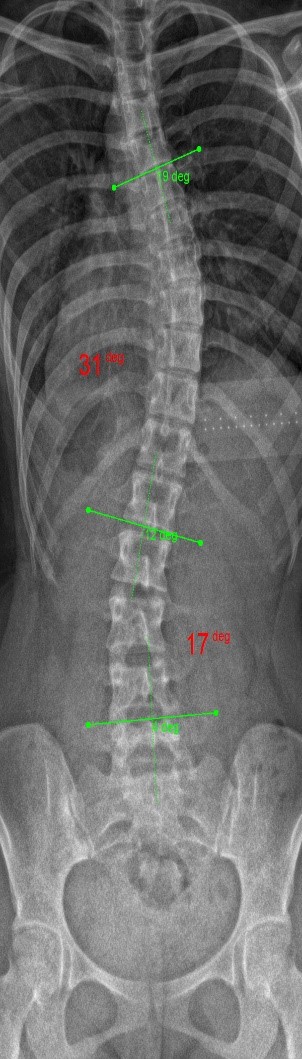

The clinical test results show that the SCN800 series is highly consistent with the X-ray, with a linear correlation of 0.94, similar results have also been published in SCI articles (Lee TT, Lai KK, Cheng JC, Castelein RM, Lam TP, Zheng YP. 3D ultrasound imaging provides reliable angle measurement with validity comparable to X-ray in patients with adolescent idiopathic scoliosis. Journal of Orthopaedic Translation. 29:51-59, 2021).

In our clinical trials and studies, we measured two angles to facilitate comparison. X-rays can actually show 3 to 4 angles, some in the neck and bottom area. Ultrasound images can also measure angles near the neck like an X-ray.

The following images compare 5 ultrasound and X-ray clinical measurement examples: